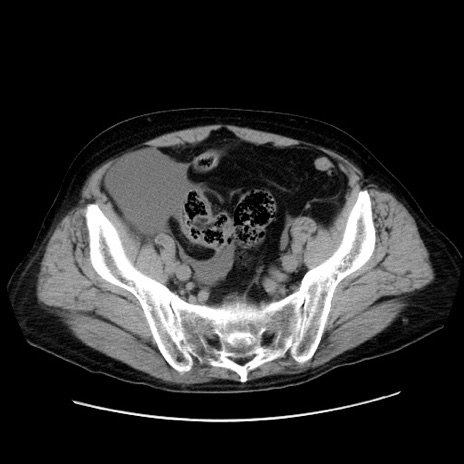

症例30(横断像)

【症例】80歳代男性

【主訴】臍周囲痛

【現病歴】約6時間前から臍下部痛が出現。次第に腹部膨隆・背部痛も生じてきたため来院。背部痛の場所は変化しない。

【身体所見】意識清明、BT 36.3℃、BP  131/87mmHg、P 87bpm、SpO2 100%(RA)、臍周囲自発痛・圧痛あり、反跳痛なし、自発痛部位に一致して板状硬あり、腹部膨隆、腸雑音減弱、CVA tenderness両側陰性。

【データ】WBC 19600、CRP 0.33